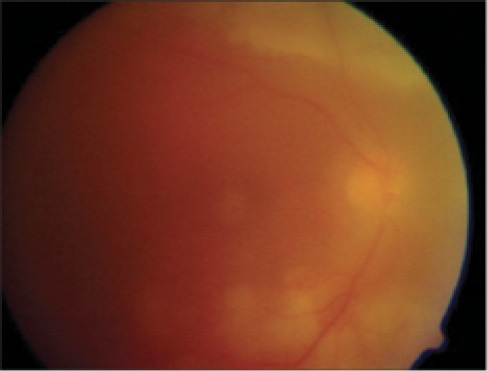

Figure. Although the US Food and Drug Administration relies on vitreous haze as the primary surrogate endpoint for uveitis, this clinical finding is not always the primary feature of the condition and is thus an unreliable sign. The 1 to 2+ vitreous haze in this image is so borderline that different clinicians could easily interpret it differently.

However, there were unforeseen consequences to this effort as well. Given the difficulty of describing various posterior findings of uveitis and the relative infancy of ocular imaging, a consensus could not be achieved on the quantification of many posterior parameters beyond vitreous haze (Figure). This, unfortunately, has led to the over-reliance on vitreous haze as a marker of disease activity, especially in clinical trials regarding intermediate, posterior, and panuveitis. Vitreous haze has become the primary surrogate endpoint for these types of uveitis as far as the US Food and Drug Administration is concerned. Most ophthalmologists are aware of cases in which vitreous haze was not the primary feature of disease, and they understand how unreliable vitreous haze can be in this regard.